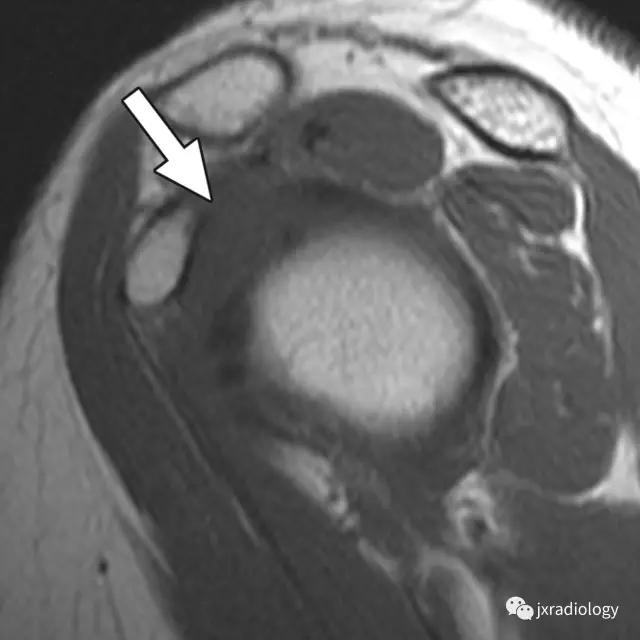

2、肩袖间隙周边稳定肱二头肌腱长头(LBT) 的滑轮结构创伤性病变 , 如肩胛下肌腱、SGHL-MCHL 复合体、外侧CHL等损伤 。

病例图示:

文章插图